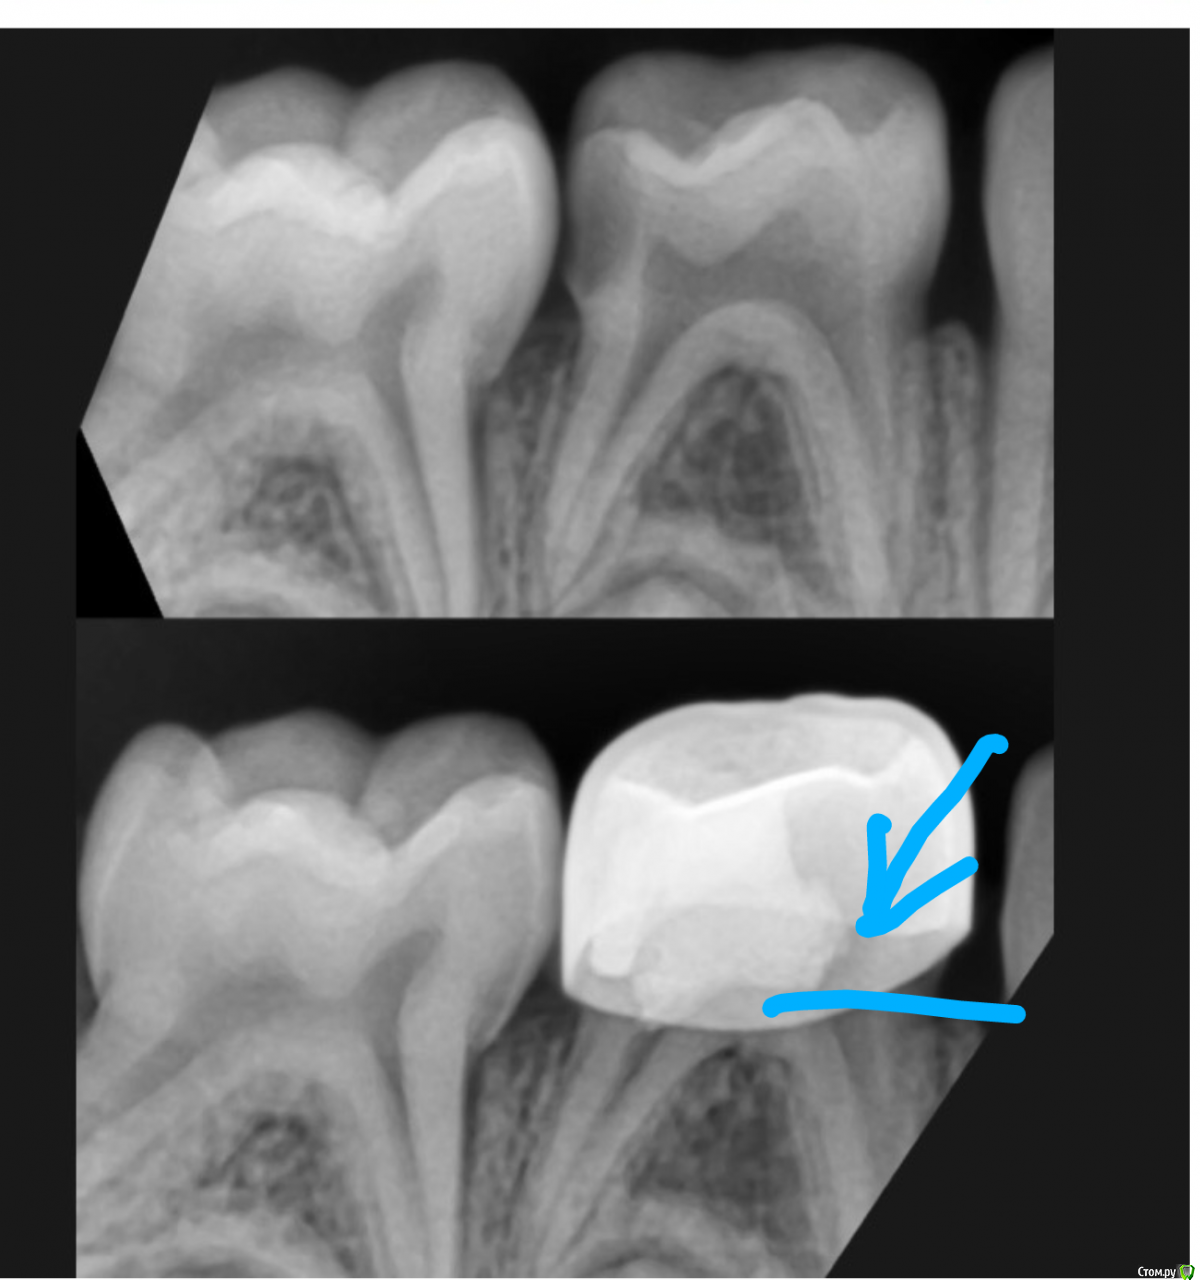

CRAZYDUCK Опубликовано 15 июля, 2018 Автор Поделиться Опубликовано 15 июля, 2018 https://c.radikalНе хочется коронку , но дистальная стенка очень тонкая , почти прозрачная (указала стрелкой ), даже голубой платок через неё видно. Ребёнку 5 лет , значит -пломба должна простоять ещё лет 5. А пломба такого размера не простоит 2 Ссылка на комментарий

CRAZYDUCK Опубликовано 26 июля, 2018 Автор Поделиться Опубликовано 26 июля, 2018 Лечение 8.5 ( в каналах йодотин , коронка), удаление 8.4.Удаляю в коффердаме ( если в это же посещение лечение , если запись только на удаление - специально коффердам не одеваю. Изолирую , лечим 8.5, фиксирую коронку , растягиваю платок и удаляю 8.4 , потом снимаю коффердам . В коффердаме не видно щипцов . Ещё перед удалением в коффердаме же добавляю анестезию . 1 Ссылка на комментарий